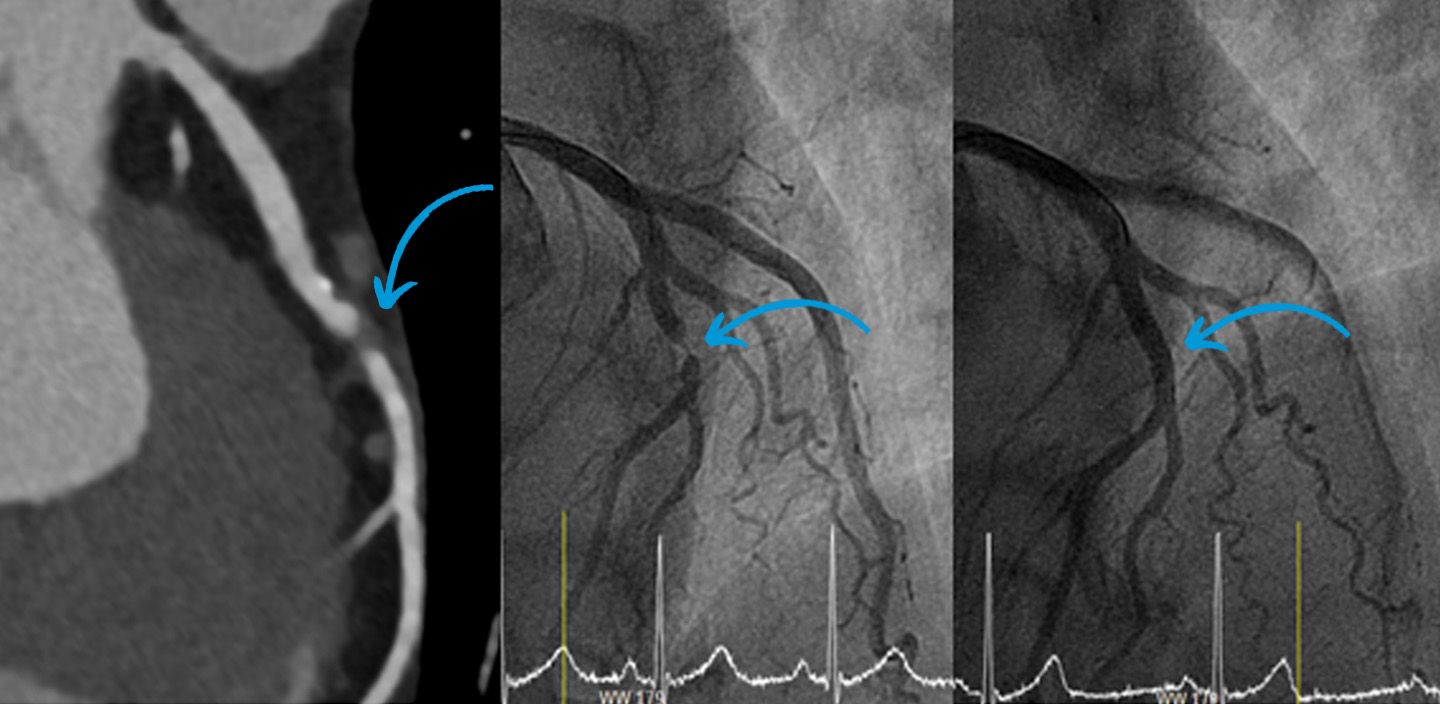

52jähriger Mann mit hochgradiger Verengung eines Asts der linken Herzkranzarterie (Koronarstenose des RIVA).

Links: Computertomographie CT der Verengung

Mitte: Invasive Koronarangiographie vor Intervention.

Rechts: Invasive Koronarangiographie nach Intervention mit Stentimplantation.